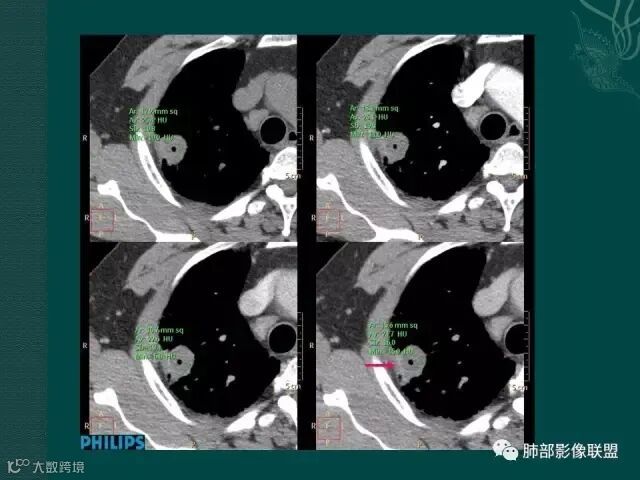

厚壁,大部分坏死,外缘较清晰,穿刺时千万不要穿坏死区;

鳞癌破坏力在所有类型肺癌中,都是最强的,所以出现坏死的几率特别是大片坏死的概率,是远远高于腺癌。